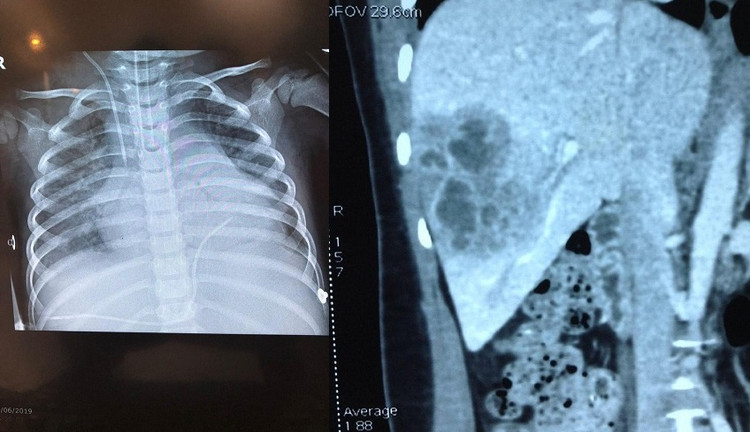

![]() |

| Ảnh xquang em bé 3 tuổi bị tràn dịch đa màng: Màng bụng, màng tim, màng phổi do sán lá gan lớn |

| Tổn thương tại gan do sán lá gan ở bệnh nhi 3 tuổi |